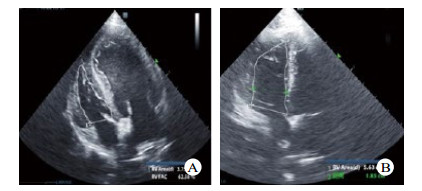

| A:为瑞士HAMILTON·G5呼吸机;B:肺动脉漂浮导管位置 图 1 本实验所用呼吸机及心脏超声机 Fig 1 Ventilator and echocardiography used in this experiment |